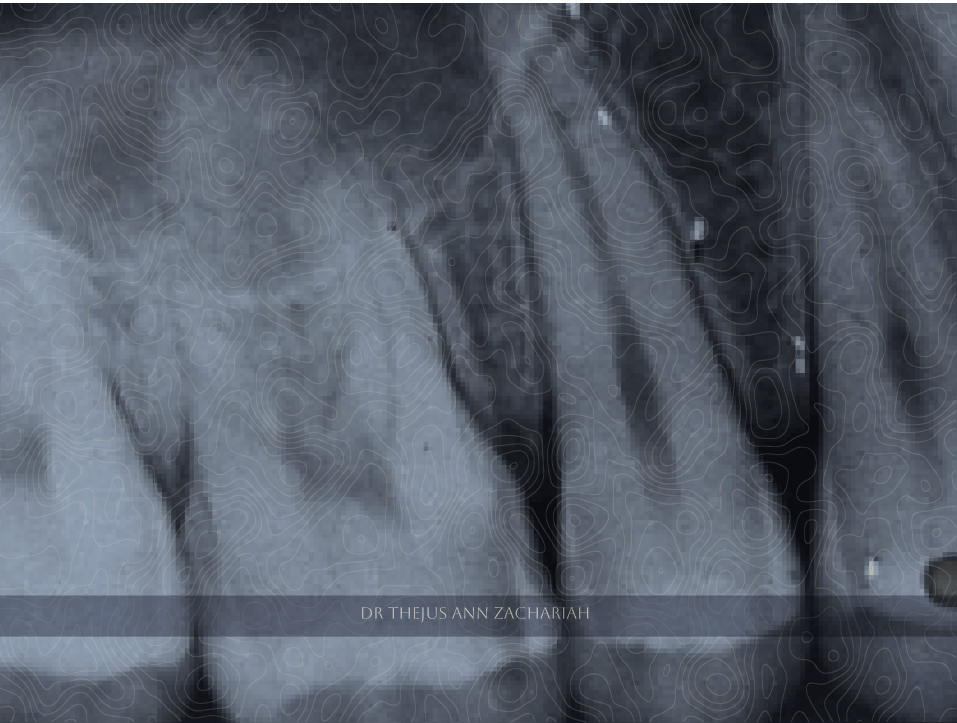

Pre-Operative

alt text

Pre & Post-Operative X Ray

alt text alt text